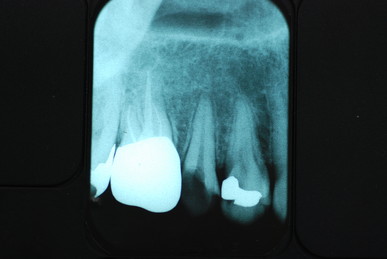

今日も歯の中の治療後、痛くて眠れなくなり“まともな歯医者”を探して遠方より患者さんが来られました。

今日来た方もお話しから刺し歯が取れた後最初に受診した歯科医院で、神経があった所にばい菌があるので綺麗にした後被せ治しましょうという説明を受け、ばい菌が残っている“根幹”という神経がもと存在した穴を探し掃除をしていたようですが、まだ歯の中には虫歯というばい菌の塊が残っていました。

そして相当歯と歯の間の歯の部分の崩壊が激しくこの部分を何かで封鎖して根幹治療をしないと、ばい菌がどんどん入る状態でほじくっても意味がないし、ばい菌が存在しやすい状態では何をやっても意味がないような気がします。

下のレントゲンの真ん中の欠けた歯が痛くて来られました。

虫歯というばい菌を除去して壁を作り歯のような形にしてから根幹治療をしないと痛くなりやすいのです。

DSC_0001

今回は時間がないので歯の治療は殆どせず、歯の中の洗浄を行い硬いセメントで封鎖しました。

一番奥の銀歯の裏側(舌側)にものすごい虫歯ができていて

穴があいて心配になり受診されました。

セトモノや銀歯を被せたと言っても治った訳ではないのです。

銀歯を外すと歯茎との境目が虫歯という“ばい菌”の塊でボロボロ

でした。

ばい菌を除去した後の歯です。神経を取り削り被せた歯というのはセトモノであろうと銀歯であろうとこのように殆ど健康な部分はないのです。

磨かなければ、磨けなければ“助からないのです。”